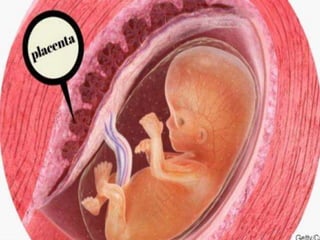

El desprendimiento prematuro de placenta normoinserta es la separación de la placenta de su sitio normal de implantación antes del nacimiento del feto, ocurre en el 30% de los casos de sangrado en el tercer trimestre. Puede presentarse con hemorragia externa visible o hemorragia oculta interna, siendo esta última forma más grave con mayor riesgo de complicaciones como coagulopatía y muerte fetal. El tratamiento consiste en reposo absoluto, monitoreo continuo y control del sangrado a través de ecografía y transfusión si es neces